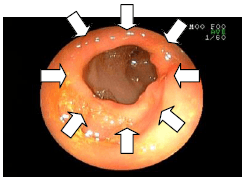

2. 胃の中のヒモを取り出した例

![]() |

ヒモを飲み込んでしまった猫の胃の内視鏡画像です。 ヒモが胃の中で絡まっているのが見えます。(矢印) |